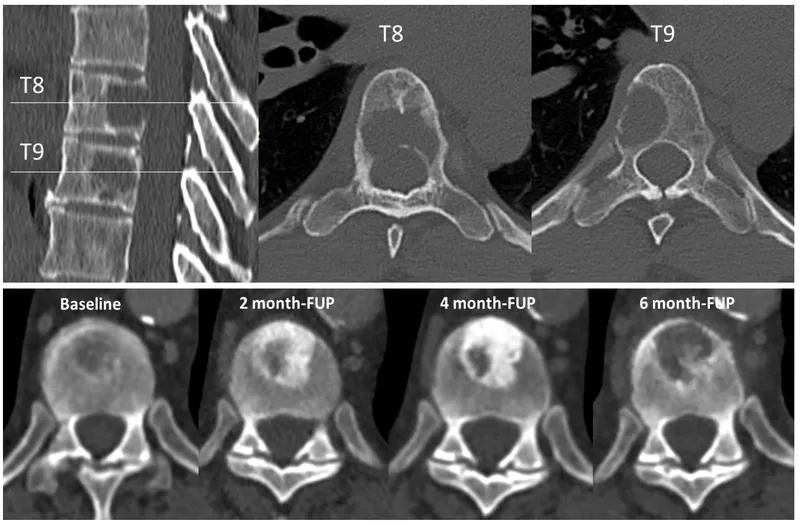

- MRI: Marrow, soft tissue, cord compression.

- CT: Bone detail, biopsy guidance.

- Tokuhashi Score (Revised): Estimates survival for spinal metastases.

- Factors: KPS, extraspinal mets, vertebral mets, visceral mets, primary cancer, palsy.

- Score 0-8: Poor prognosis (< 6 months survival).

- Score 12-15: Better prognosis (> 12 months survival).